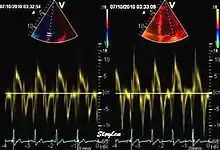

Like Doppler flow, tissue Doppler can be acquired both by spectral analysis (spectral density estimation) as pulsed Doppler[1] and by the autocorrelation technique as colour tissue Doppler[2] (duplex ultrasonography). While pulsed Doppler only acquires the velocity at one point at a time, colour Doppler can acquire simultaneous pixel velocity values across the whole imaging field. Pulsed Doppler on the other hand, is more robust against noise, as peak values are measured on top of the spectrum, and are unaffected of the presence of clutter (stationary reverberation noise).

This has become a major echocardiographic tool for assessment of both systolic and diastolic ventricular function. However, as this is a spectral technique, it is important to realise that measurement of peak values is dependent on the width of the spectrum, which again is a function of gain setting.

Pulsed wave spectral tissue Doppler has become a universal tool that is part of the general echocardiographic examination. Like any other echocardiographic measurement, measures by tissue Doppler should be interpreted in the context of the whole examination. The velocity curves are in general taken from the base of the mitral annulus at the insertion of the mitral leaflets, in the septal and lateral points of the four chamber view, and eventually the anterior and inferior points of the two-chamber views. For the right ventricle it is customary to use the lateral point of the tricuspid annulus only. Averaging peak velocities from the septal and lateral point has become common, although it has been shown that averaging all four points mentioned above, gives significantly less variability[3]

The method measures annular velocities to and from the probe during the heart cycle.

Annular velocities summarize the longitudinal contraction of the ventricle during systole, and elongation during diastole. Peak velocities are commonly used.